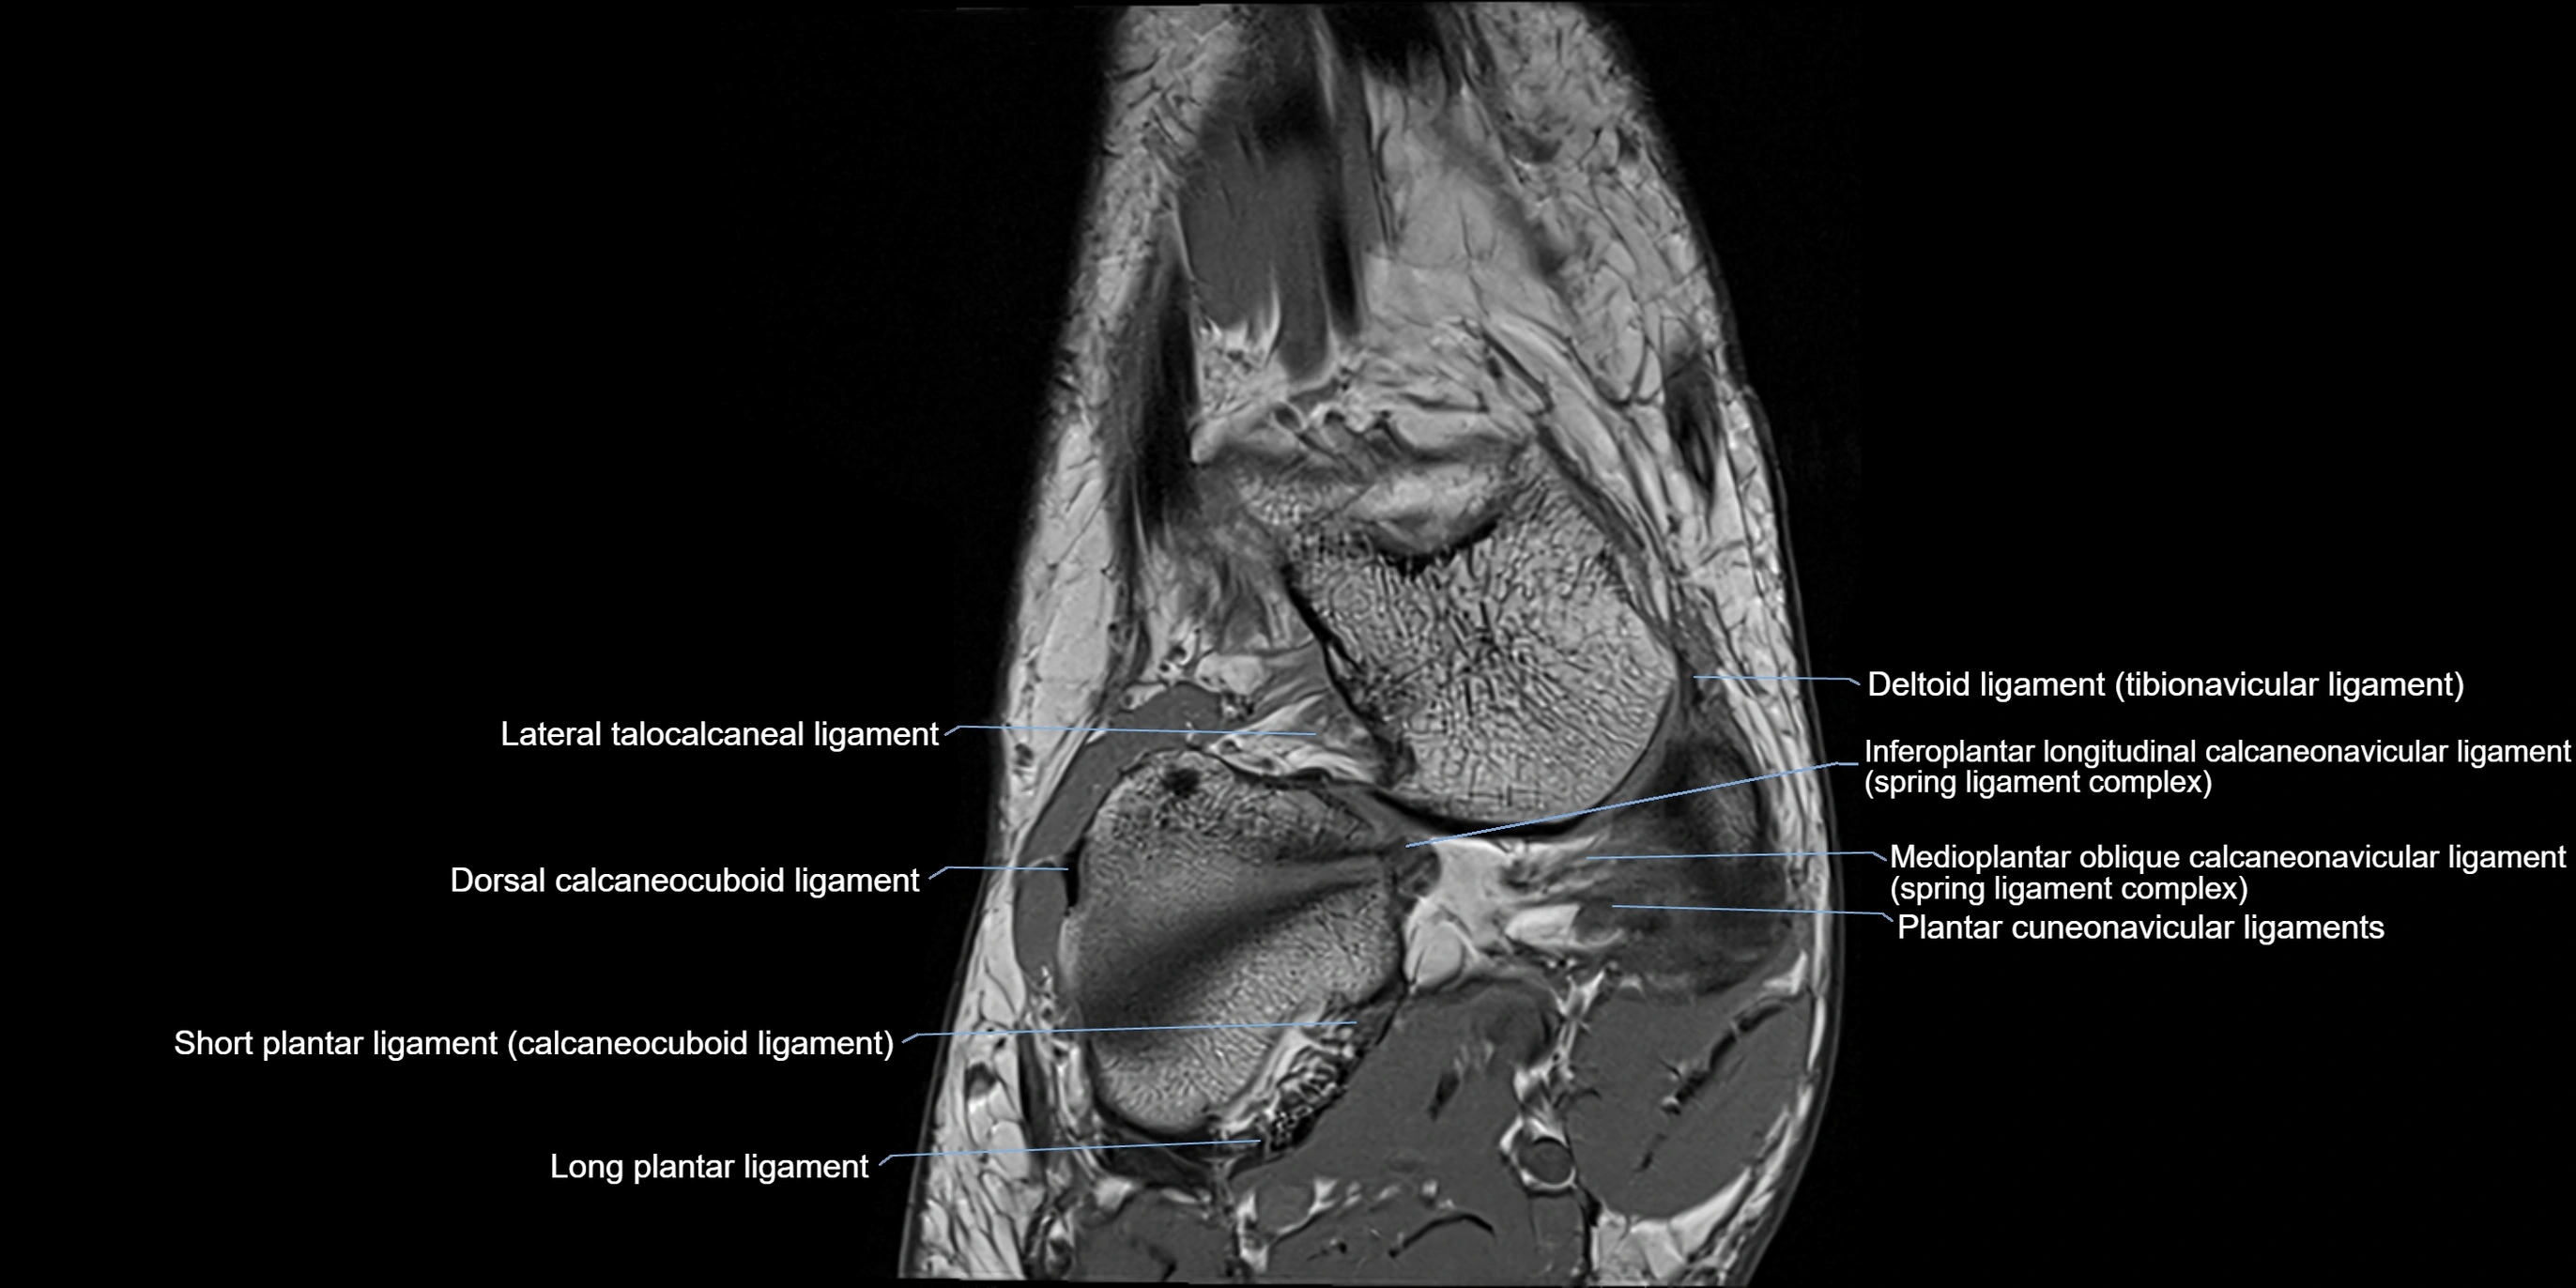

MRI image

image